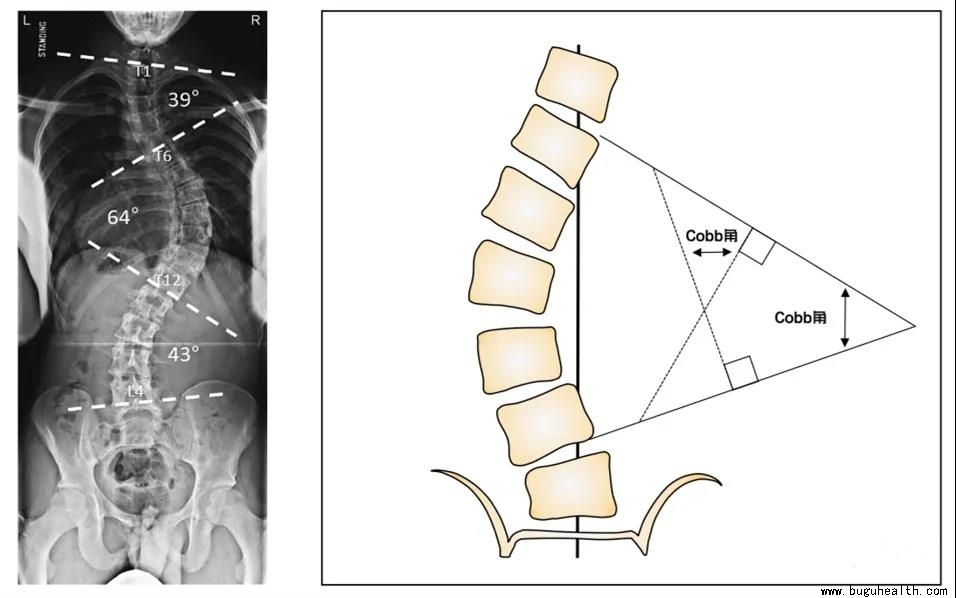

脊柱侧弯,顾名思义就是脊柱的侧向弯曲,指脊柱偏离人体的中轴线,出现了侧方的弯曲伴有椎体的旋转的三维脊柱畸形。国际脊柱侧弯研究学会(Scoliosis Research Society,SRS)将脊柱侧弯定义为——站立位脊柱正位X片Cobb角测量大于10°。

Cobb角,侧弯上下最倾斜的两个椎体,也就是端椎,沿上端椎上缘和下端椎下缘分别画两条射线,再做两条线的垂线的相交形成的角。